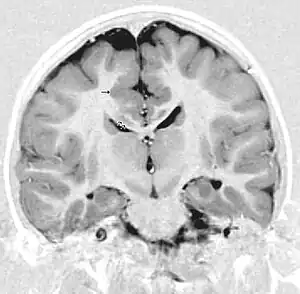

| This child presented with seizures. The coronal true inversion recovery sequence shows thickened and disordered cortex in superior frontal and cingulate gyri bilaterally (arrow). There are small convolutions visible at the corticomedullary junction. The appearance is that of cortical dysplasia, with polymicrogyria more likely than pachygyria due to the small convolutions visible. There are also small foci of grey matter signal in the corpus callosum, deep to the dysplastic cortex (double arrows). These probably represent areas of grey matter heterotopia. | |